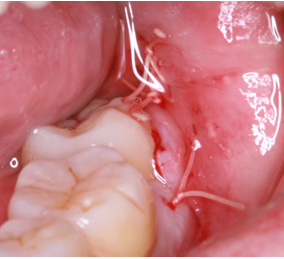

※歯肉の切開、出血を伴う写真がございます。

2回法親知らずの抜歯処置を表示する

処置の流れ

まず歯冠を切除し、疼痛がでないよう、冠部歯髄を除去してネオダイン(歯髄の鎮痛鎮静、象牙質の消毒、覆髄)を填入します。その後、粘膜骨膜弁にて完全閉鎖を行います。以下に処置の流れを示します。